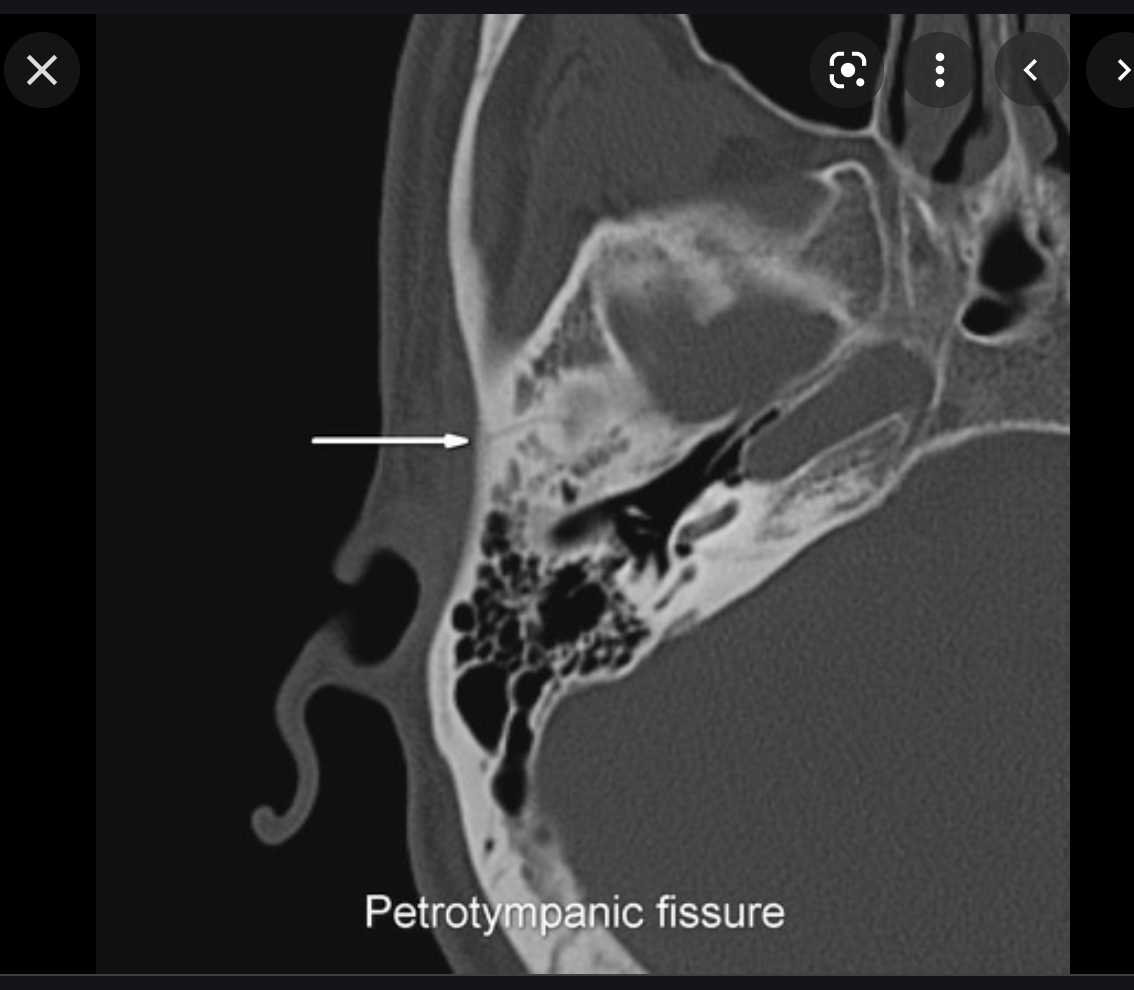

CT

High-density bone deposition within the membranous labyrinth:

mild disease: hazy increase in density within fluid spaces of the membranous labyrinth

moderate disease: focal areas of bony encroachment on fluid spaces of the membranous labyrinth

severe disease: membranous labyrinth completely obliterated by bone replacing fluid spaces

The term otosclerosis is somewhat of a misnomer. Much of the clinical course is characterised by lucent rather than sclerotic bony changes and hence it is more appropriately known as otospongiosis which is a term preferred by many head and neck radiologists.